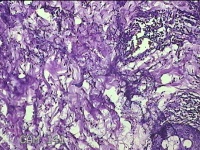

右腋下结节

性别

男

年龄

37岁

临床诊断

腋窝乳糜囊肿

一般病史

发现右腋下结节1年余,近日出现局部红肿及疼痛。

标本名称

大体所见

灰白暗红色组织2.7x1.8x0.8cm一块,表面带梭形皮肤2.8x1.3cm,皮下见结节2.7x1.3cm一个,切开结节呈实性,切面灰白粉红色,质软。

慢性脓肿

皮肤慢性炎症伴局灶性化脓性炎症。

所提供图片不具有诊断价值,炎性病变可能。